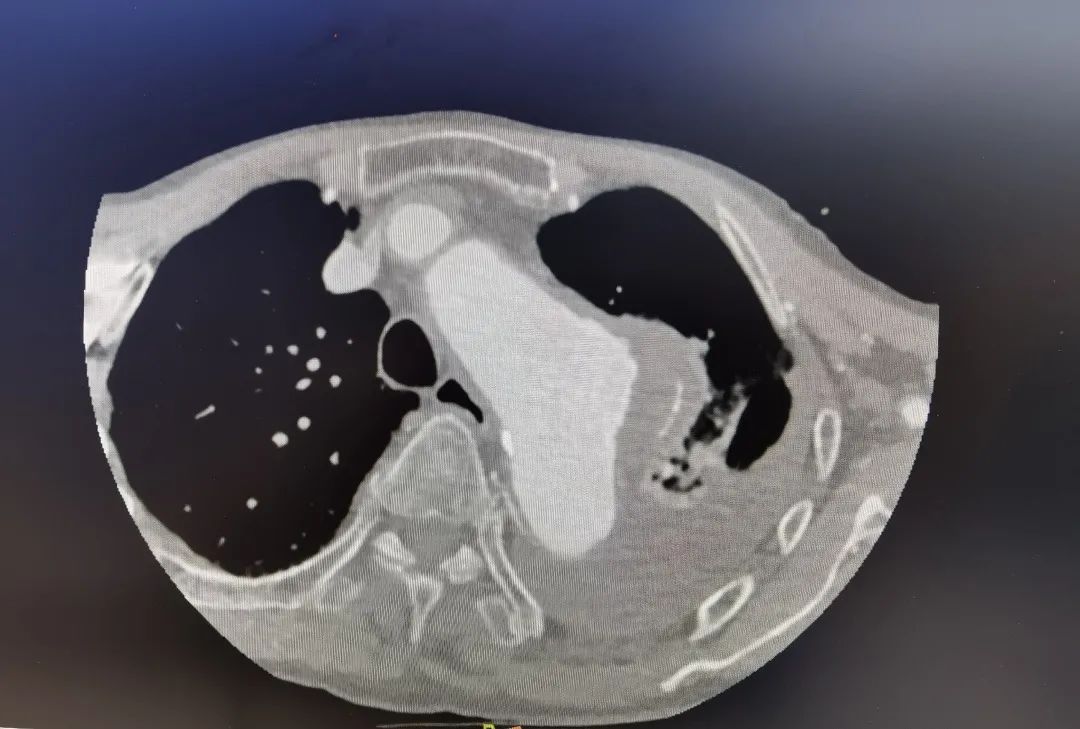

“患者被送到医院时,一直说胸口痛,如果体内有胸动脉瘤,这往往是瘤子要破裂的征兆。从CT影像来看也确实如此,造影剂已从主动脉瘤渗漏出来,说明瘤子即将破裂。另外,患者左侧胸腔大量积水,这也是动脉瘤破裂的先兆。”接诊的华体会体育 心外科副主任医师伍源解释说,种种迹象表明,林大爷体内的动脉瘤随时可能破裂大出血迅速导致死亡,必须尽快手术。